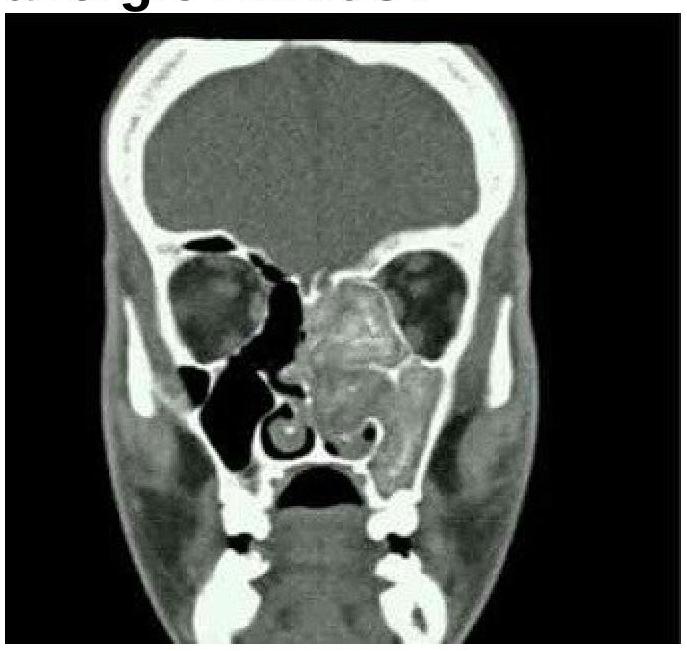

What is the most likely finding in the CT image of the left maxillary sinus in a patient with a history of allergic rhinitis?

Explanation: ***Ground-glass opacity*** - This image shows diffuse opacification of the left maxillary sinus with a characteristic **ground-glass appearance**, which is often associated with allergic fungal rhinosinusitis (AFRS), a condition that can complicate allergic rhinitis. - The patient's history of **allergic rhinitis** makes AFRS a strong consideration, and the CT finding of ground-glass opacity within the sinus lumen is a classic imaging feature of this condition, representing fungal elements and mucin. *Honeycomb appearance* - A **honeycomb appearance** on CT is typically seen in the lungs and indicates **pulmonary fibrosis**, characterized by clustered cystic airspaces with thickened walls. - This finding is not associated with paranasal sinus pathology, especially not with allergic rhinitis or its common complications. *Onion peel appearance* - The **onion peel appearance** on imaging refers to periosteal reaction with multiple concentric layers of new bone formation. - This is a hallmark feature of conditions like **Ewing sarcoma** and chronic osteomyelitis, primarily affecting bone, not the soft tissue or mucosal lining of a sinus in the context of allergic rhinitis. *Double density* - **Double density** is a term primarily used in echocardiography to describe specific findings related to left atrial enlargement, or occasionally in chest radiography where it might represent superimposed densities. - This term does not describe a finding relevant to paranasal sinus pathology on CT imaging.